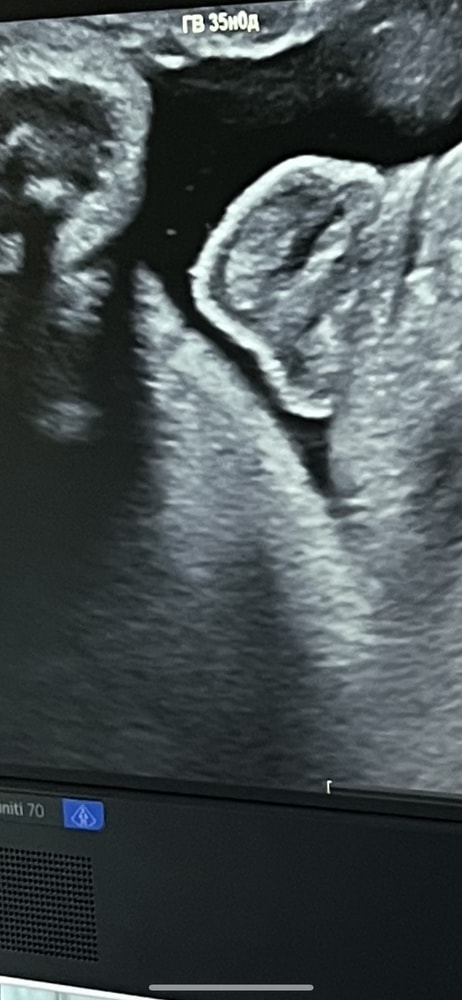

Помогите,Тут какой пол видно? Девочка или мальчик ? 34 неделя снимок